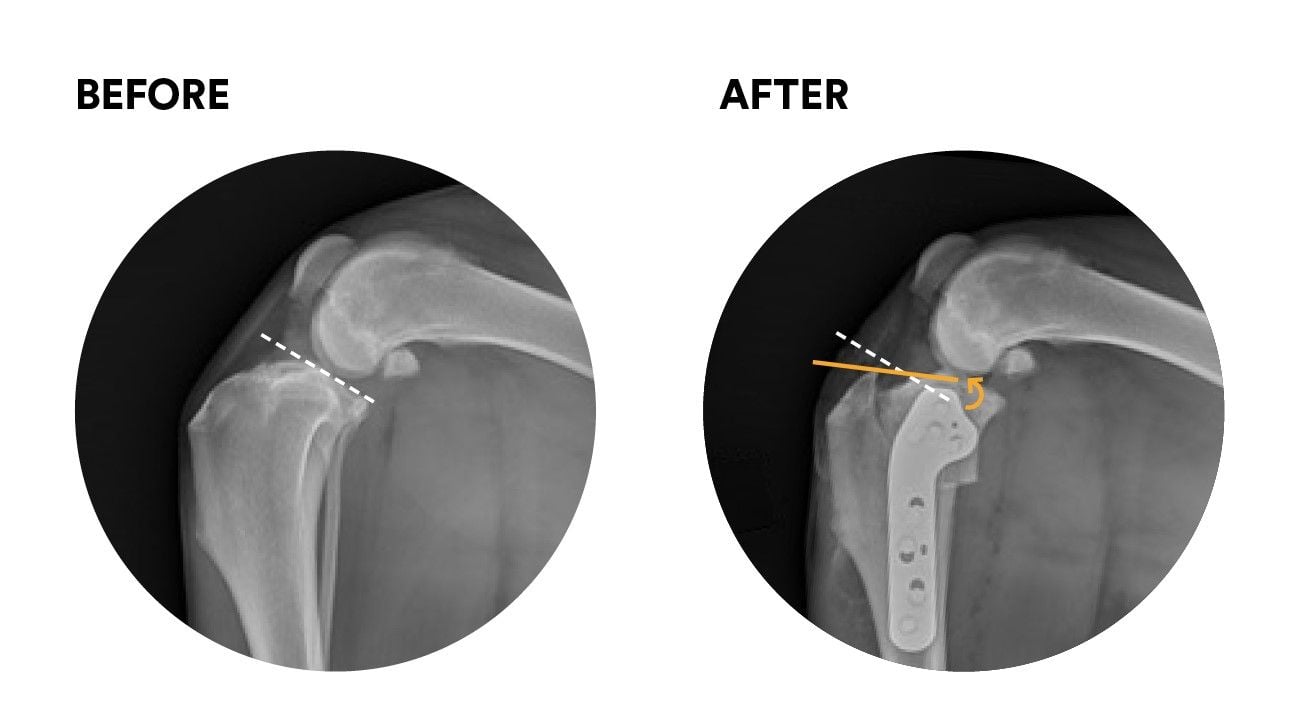

Tibial plateau Levelling osteotomy or TPLO is a procedure for managing stifle instability due to failure of the anterior cruciate ligament, also know as the cranial cruciate ligament.

TPLO surgery falls into the second category and is the originator of this concept. The joint is altered and no longer requires the cruciate to be stable during loading.

- The TPLO procedure - The proximal tibia is approached through a small incision and the tibia is cut with a curved saw and the bones altered in position. Finally a plate is applied to hold the bones in position while they heal.